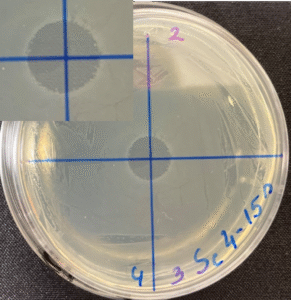

Photos of the Petri plates, 72 hours after bacterial (Streptococcus canis) inoculation.

The image and the inset show complete (positive) bacterial growth inhibition (full translucency)

at the treatment site after one dose of UV-C for 15 seconds at a 10 mm distance.

The blue lines divide the plate into quadrants.